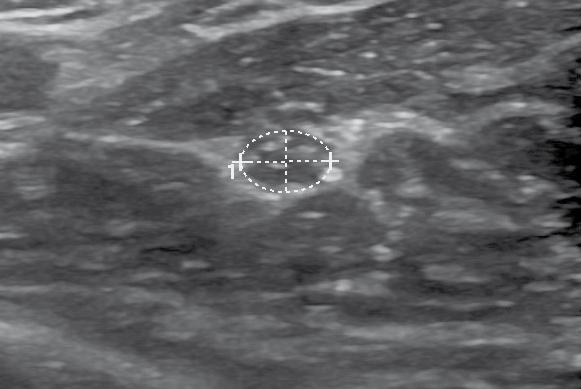

Patienten-/Prozedurinfo Bildgebung

Vorher/Nachher

Covid Thrombus

Aufgrund der erhöhten Blutungskomplikatio nen sollte wann immer möglich keine Lyse mehr durchgeführt werden und idealerweise nur noch rein mechanisch gearbeitet werden. Das hat eine Metaanalyse eindrücklich zeigen können12. Zwar fand sich kein Unterschied beim Lysegrad bei der mechanischen Thrombektomie und der Lyse, je doch signifikant mehr Blutungskomplikationen bei der Lyse12

Was ist neu?

Dank moderner Devices für die minimal invasive, perkutane Thrombektomie können nun auch gros se Thrombusmengen aus dem peripheren Gefäss sytem bei tiefer Beinvenenthrombose entfernt werden. Dies geschieht im Rahmen eines minimal invasiven Eingriffs, idealerweise ohne die Anwen dung von Thrombolytika und dementsprechend auch ohne Überwachung auf einer Intensivstation. Die Durchführung ist bei manchen Fällen sogar in einem ambulanten Setting möglich.

Die Ergebnisse der mechanischen Thrombek tomie sind vielversprechend, wie auch eine Zwischenanalsyse bei 250 Patienten aus dem CLOUT-Register (Studie veröffentlicht im Feb ruar 2022, QR-Code siehe rechts unten) zeigen konnte. Nach sechs Monaten zeigte sich eine vollständige oder nahezu vollständige Throm busentfernung in 85% der Fälle (akut: 90%; sub akut 81%; chronisch: 84%), einschliesslich 51% der Fälle (akut: 54%; subakut: 49%; chronisch: 49%) mit 100% Thrombusentfernung. Fast alle (99,6%) Eingriffe wurden in einer einzigen Inter vention durchgeführt, bei keinem Patienten wur den Thrombolytika eingesetzt und der mediane Blutverlust war mit 50 ml vernachlässigbar. Sig nifikante Verbesserungen wurden bei mehreren Messungen der Lebensqualität bis zu 6 Monate beobachtet, darunter 92,2% der Patienten, die frei von einem mittelschweren oder schweren post thrombotischen Syndrom (PTS) waren.

Halb geleert klebriger CovidThrombus am Netz. Voll mit Thrombus.